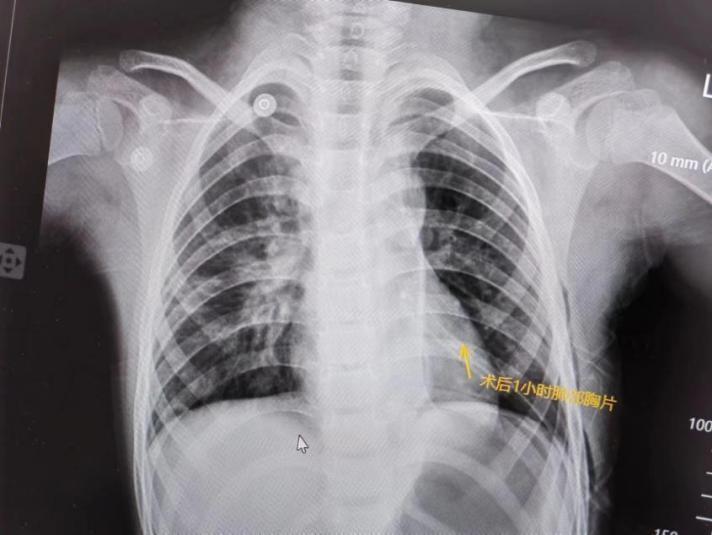

手术后,多多病情平稳,剩余肺叶通气膨胀良好,虽然手术带来的疼痛让她每一次呼吸都小心翼翼;但是她坚毅而倔强的小眼神里闪烁的都是欢喜。多多的父母术后紧紧握住曹主任的手说:“太谢谢您了,困扰我们六年的难题终于解决了。”